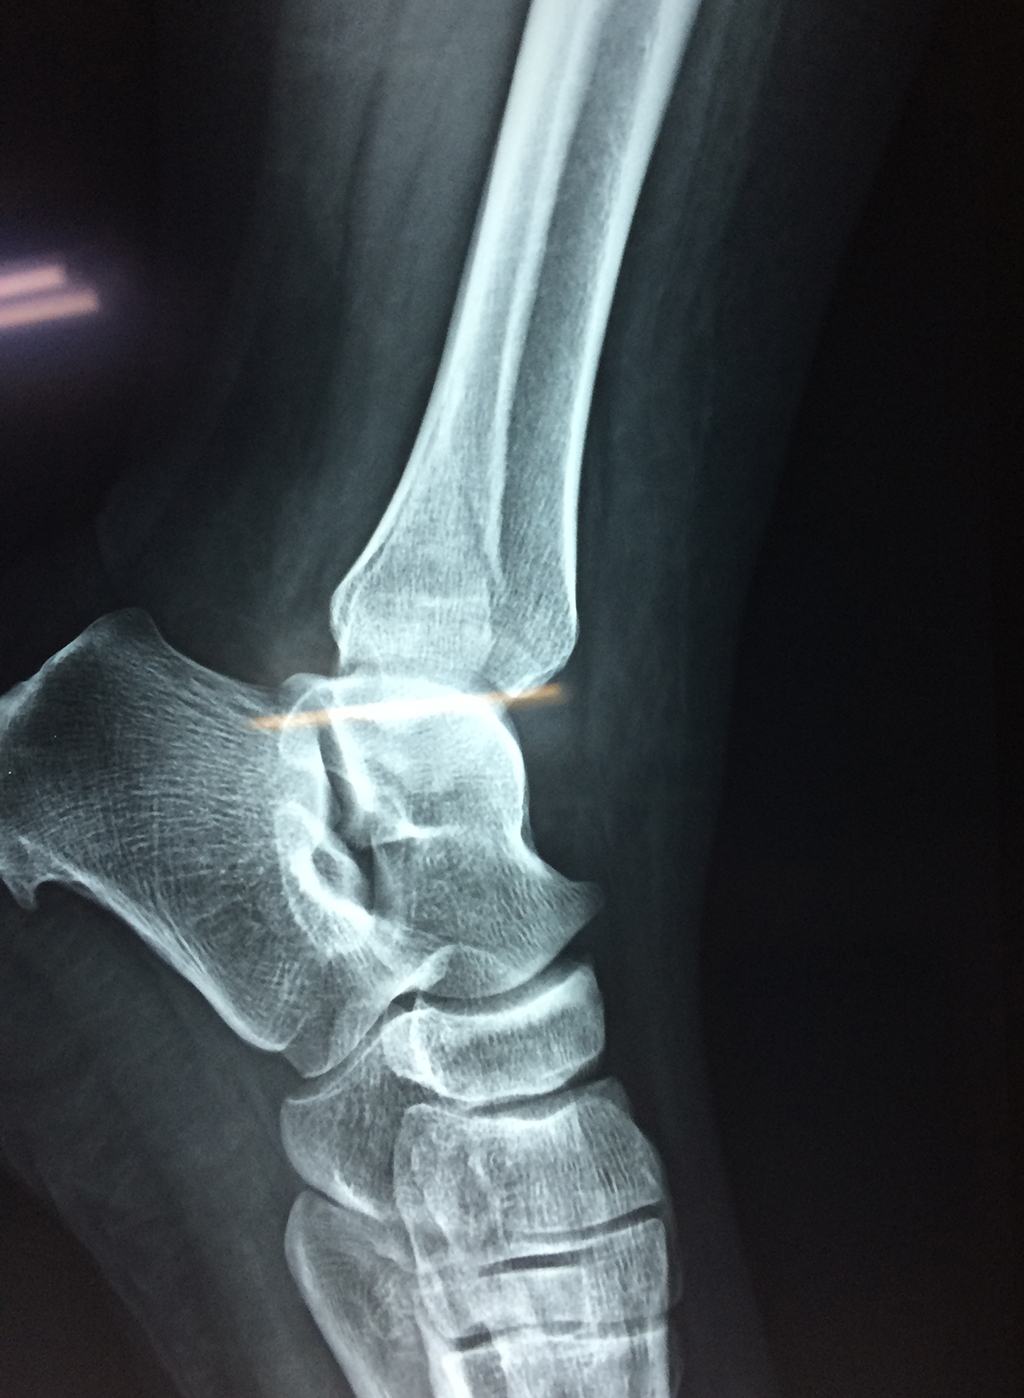

Una fractura de tobillo es la rotura de uno o más de los huesos del tobillo. Estas fracturas pueden ser:

Algunas fracturas de tobillo pueden requerir cirugía si:

- Los extremos de los huesos están desalineados entre sí (desplazados).

- La fractura se extiende hasta la articulación del tobillo (fractura intra-articular).

- Los tendones o ligamentos (tejidos que sujetan los músculos y los huesos entre sí) están rotos.

- El médico cree que sus huesos probablemente no sanen apropiadamente sin cirugía.

- El médico considera que la cirugía puede permitirle una recuperación más rápida y confiable.

- En los niños, la fractura involucra la parte del hueso del tobillo donde el hueso está creciendo.

Cuando se necesita cirugía, es probable que esta implique el uso de clavijas de metal, tornillos o placas para sostener los huesos en su lugar mientras la fractura se consolida. Los elementos de soporte pueden ser temporales o permanentes.